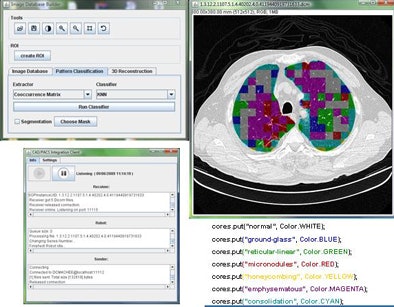

![]() |

| The DICOM open-source communication component (dm4chee toolkit) interacts with the PACS server, performing client functions DICOM C-FIND and DICOM C-MOVE. Queries directed by the DICOM header are defined for each task. The query process uses information about the modality, the anatomic region, and the imaging protocol to retrieve the requested study from the PACS server. |

| Graphic user interface of image-processing pipeline (implemented in Java) that performs five separate steps: preprocessing, segmentation, feature extraction, classification, and postprocessing. |